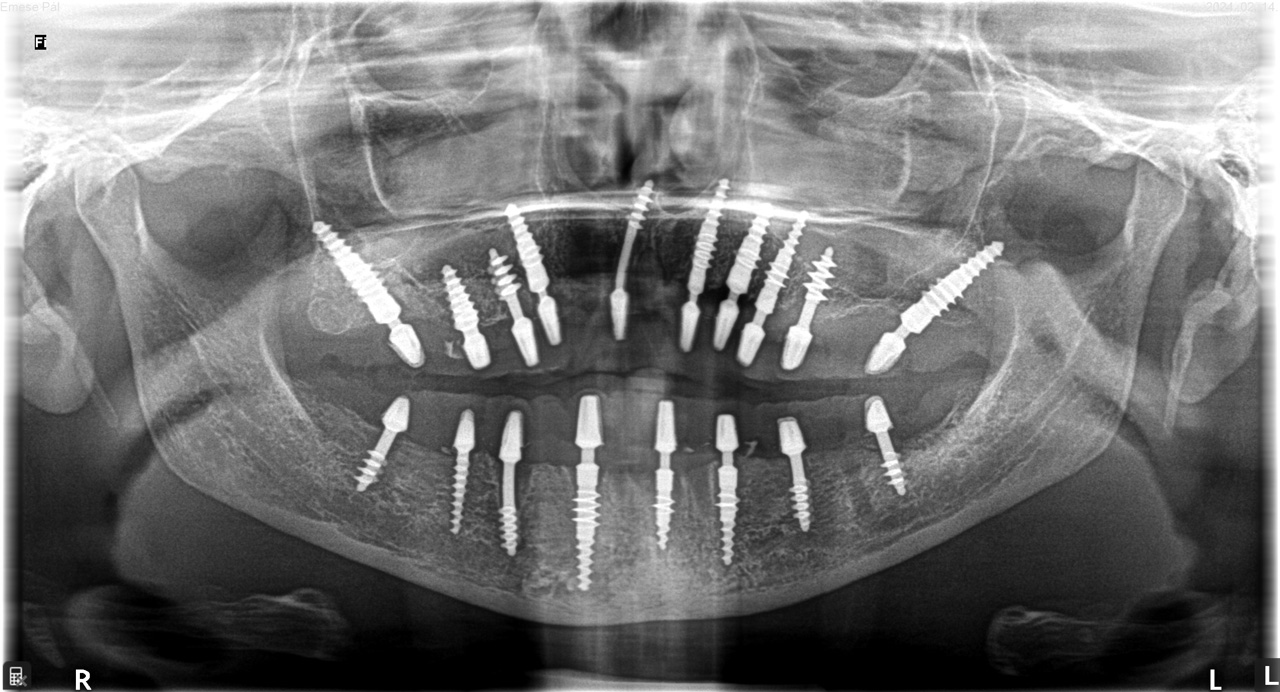

Teljes szájüregi rehabilitáció két lépésben

Ismét egy teljes szájüregi rehabilitáció két lépésben. Először az alsó fogak lettek kihúzva és azonnal implantálva, híddal ellátva, majd később a felső. IHDE svájci azonnal terhelhető implantátumok és cirkónium hidak. Dr. Kelemen Péter és a Symbion Fogtechnika közös munkája.